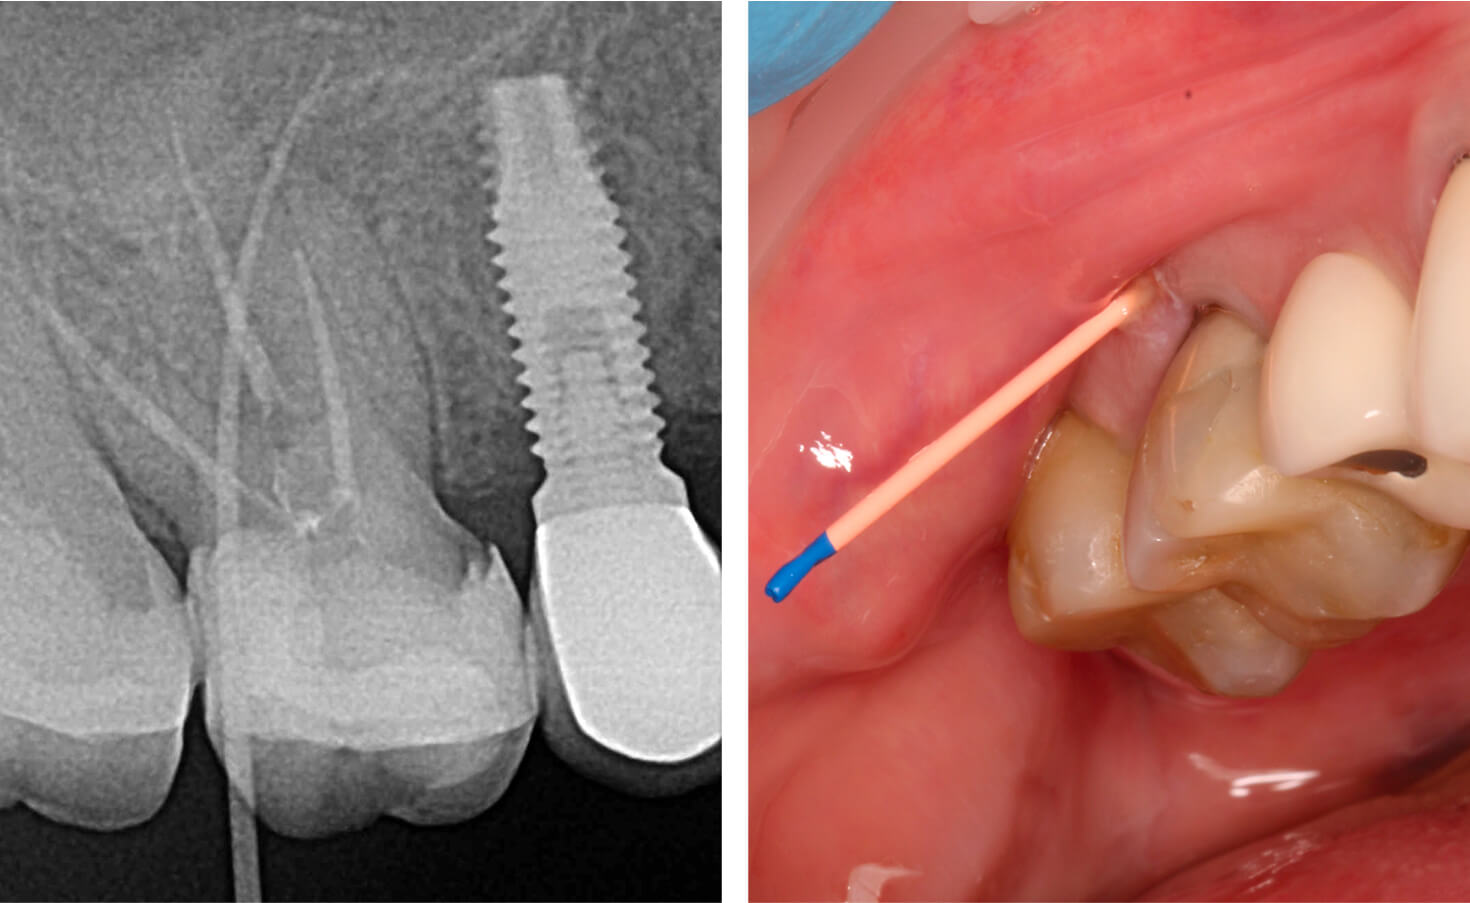

5. Контрольный осмотр через 6 месяцев, восстановление костной ткани. (Фото 9)